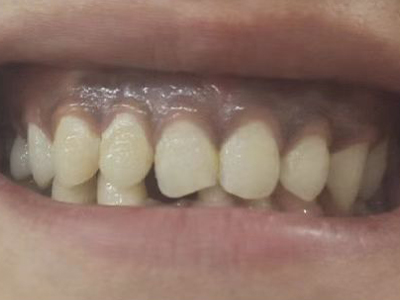

牙龈炎是发生于牙龈组织的炎症,患者可出现牙龈出血伴肿胀、发红、正常形态改变和偶尔不适等症状。本病主要由口腔卫生状况差导致,包括口腔不洁、牙菌斑等,诊断依据临床检查,治疗包括专业牙齿清洁和加强家庭口腔卫生。

牙龈炎可先引起牙齿与牙龈之间的沟(龈沟)加深,然后牙龈充血,炎症围绕一个或多个牙齿,伴牙龈乳头肿胀和易出血。一般无痛,可自行消退,也可维持轻度炎症数年。